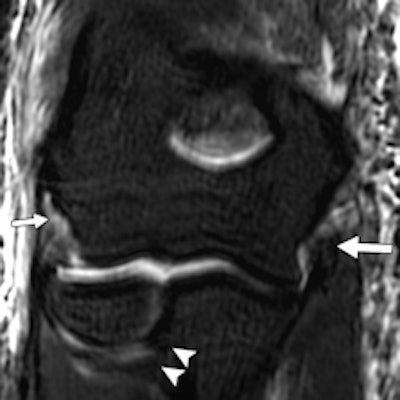

The same patient. Left: Coronal proton density-weighted fat-saturated MRI shows high-grade tear of lateral UCL (LUCL) humeral attachment (short arrow). Distal attachment of LUCL at supinator crest of ulna (arrowheads) is intact. Complete tear of UCL humeral attachment and common flexor attachment (long arrow) is seen. Right: Axial proton density-weighted fat-saturated MRI shows avulsion fracture of lateral epicondyle (long arrow). Extensive high-grade muscle tear of anterior and medial muscular compartments (short arrow) also is shown.

The same patient. Left: Coronal proton density-weighted fat-saturated MRI shows high-grade tear of lateral UCL (LUCL) humeral attachment (short arrow). Distal attachment of LUCL at supinator crest of ulna (arrowheads) is intact. Complete tear of UCL humeral attachment and common flexor attachment (long arrow) is seen. Right: Axial proton density-weighted fat-saturated MRI shows avulsion fracture of lateral epicondyle (long arrow). Extensive high-grade muscle tear of anterior and medial muscular compartments (short arrow) also is shown.Of the 28 elbows scanned for acute sports injuries, 15 had high-grade ligament injuries, and 12 of these ligament injuries occurred in contact sports and weightlifting. The remaining three injuries were seen in throwing athletes, two of whom were javelin throwers and one of whom was a volleyball player.